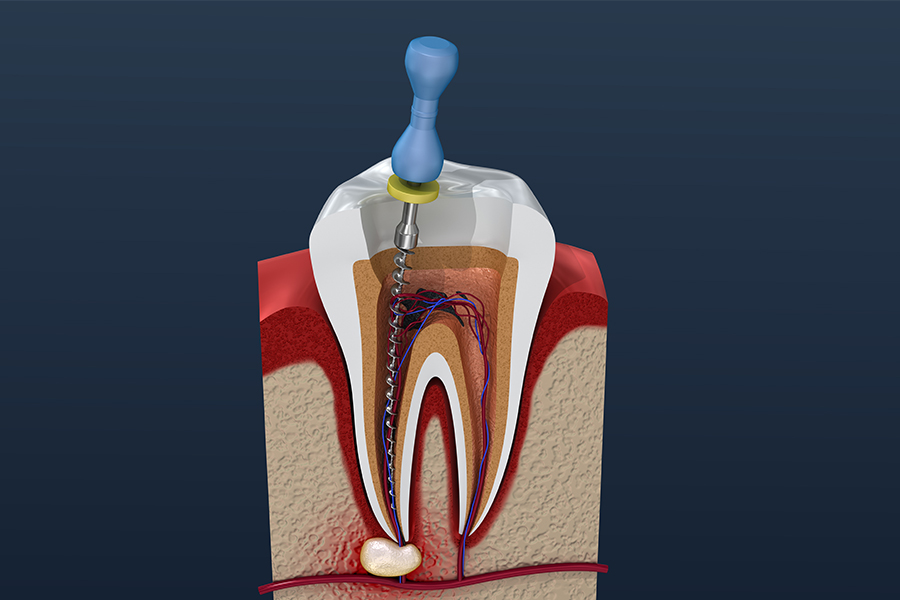

根管治療とは、虫歯が神経まで進行した歯の内部(根管)から感染した組織を取り除き、洗浄・消毒したうえで薬剤を緊密に詰めて封鎖する治療です。適切な根管治療を行うことで抜歯を避け、ご自身の歯を長く使い続けることができます。

エリナ大人こども歯科矯正歯科では、歯科用CT・拡大鏡(カールツァイス製)・ニッケルチタンファイルなどを用いた精密な根管治療を行っています。根管内部は非常に細く複雑な形状をしているため、肉眼では見落としが生じやすい治療です。精密な機器を活用することで、感染組織の取り残しを防ぎ、再発リスクを低減させます。

根管治療で最も重要なのは、根管内の細菌を徹底的に取り除くことです。当院ではニッケルチタンファイルで根管の奥まで丁寧に清掃し、薬剤で洗浄・消毒を行います。治療後は定期検診・クリーニングで再発を防止します。